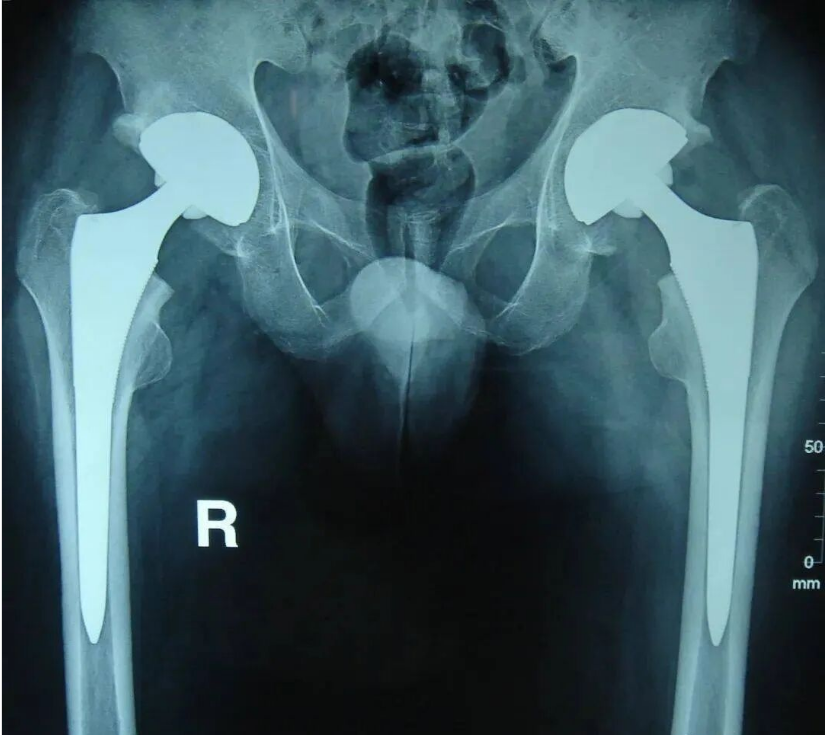

人工髋关节置换术治疗效果经过多年的临床实践已经得到充分的肯定,它是将股骨颈骨折或股骨头坏死等髋关节疾患置换为人工关节的一种治疗方法。

人工髋关节置换是指用生物相容性和机械性能良好的金属材料制成的一种类似人体骨关节的假体,利用手术方法将人工关节置换被疾病或损伤所破坏的关节面,其目的是切除病灶,清除疼痛,恢复关节的活动与原有的功能。人工关节置换具有关节活动较好,可早期下地活动,减少老年病人长期卧床的并发症等优点。